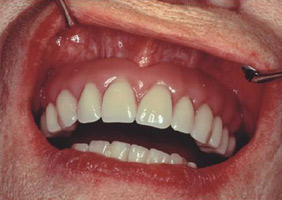

prije